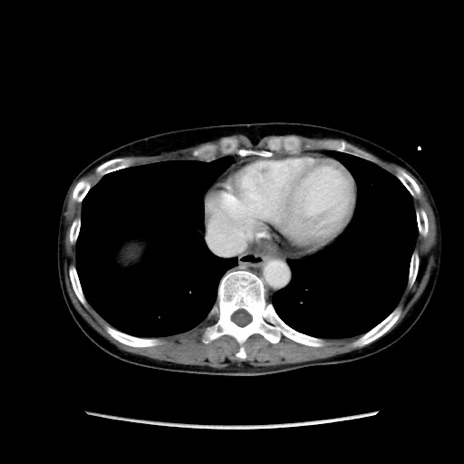

症例32(横断像)

【症例】40歳代 女性

【主訴】上腹部痛、嘔気・嘔吐

【現病歴】約9時間前頃から急に上腹部痛、嘔気、嘔吐が出現。改善しないため救急要請。

【既往歴】子宮頚癌(広汎子宮全摘術、放射線療法)、腸閉塞

【身体所見】腹部:平坦、軟、腸雑音亢進、上腹部を中心に腹部全体に圧痛あり。

【データ】WBC 8400、CRP 0.03